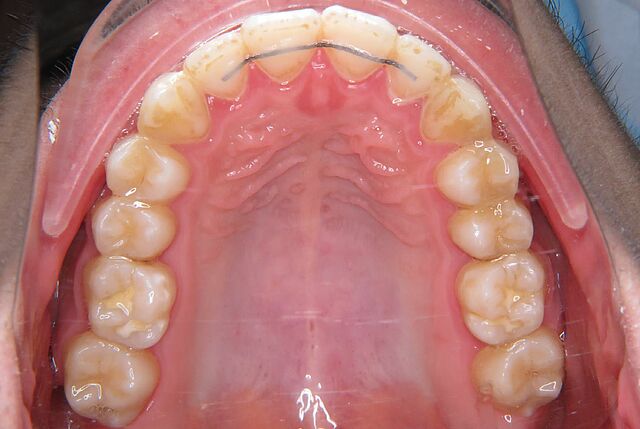

Europaweit unter den 5 größten Invisalign-Spezialisten

Das Eltz Institut für Kieferorthopädie ist seit der Europaeinführung von Invisalign® im Jahr 2001 zertifizierter Anwender. Wir haben aufgrund unserer hohen Fallzahl mit den unsichtbaren Invisalign® Zahnschienen den Diamond Apex verliehen bekommen, den höchsten Invisalign Status..